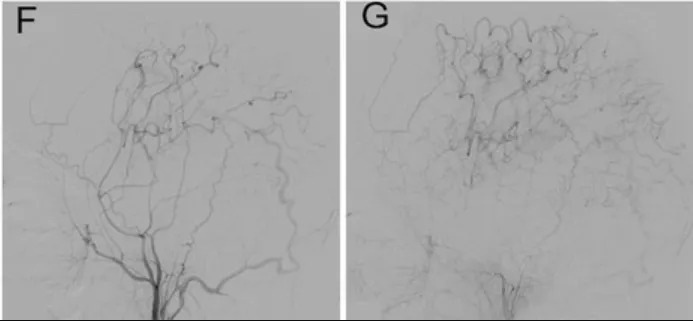

好在手术很成功。术后复查显示,新的“枕动脉-大脑中动脉”通路通畅,小智的头痛、视力模糊、肢体无力症状全没了;单光子发射计算机断层扫描(SPECT)还发现,他大脑中动脉、大脑后动脉供血区的“血管调节能力”(脑血管反应性)显著提升——这意味着大脑应对血流变化的能力变强了,未来缺血的风险大大降低。

在6个月的随访中,DSA显示先前旁路的通畅性(图F和G)